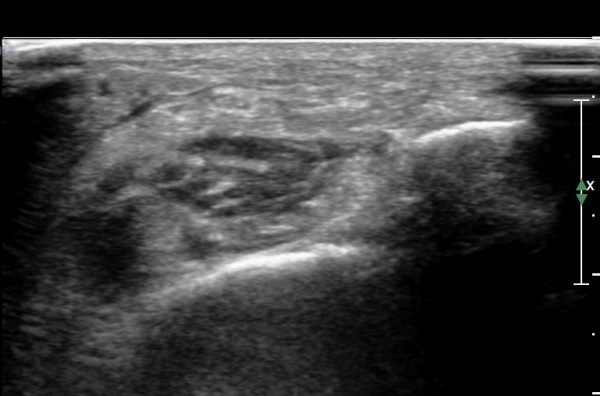

¾ÕÂÊ ¸»´Ü °æ°ñºñ°ñ°üÀý ¾à 5cm ±ÙÀ§ºÎ Ⱦ´Ü몀°Ë»ç ½Ã õºñ°ñ½Å°æ Àü¸é¿¡ Àú¿¡ÄÚ ³¶Á¾¿¡ ÀÇÇÑ ½Å°æ ¾Ð¹ÚÀÌ °üÂûµÈ´Ù(ÀÌ °üÂûµÈ´Ù(»çÁø 6, 7).

¸»´ÜÀ¸·Î °¥ ¼ö ·Ï ³¶Á¾ÀÌ Ä¿Áø°í õºñ°ñ½Å°æ ¾Ð¹ÚÀº ½ÉÇØÁø´Ù(»çÁø 8).